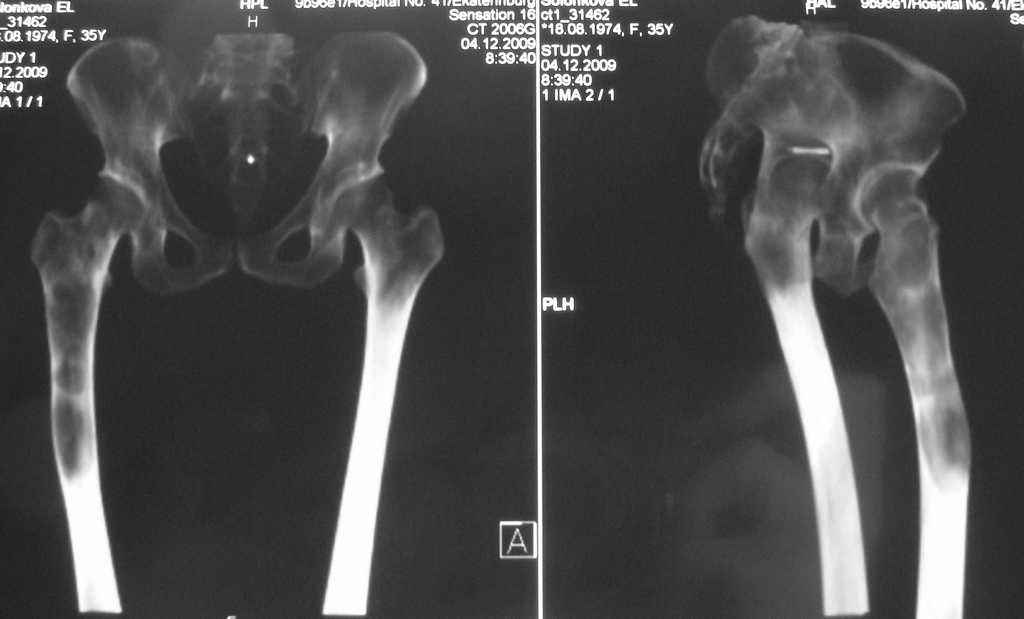

Re: Фиброзная дисплазия-продолжение

Maxim Agalakov 14 Январь 2010, 23:39

Устьянцев Ибрагимов 15 Январь 2010, 08:10

Уважаемая коллега!

Один из вариантов выбора- резекция пораженного участка, замещение дефекта по Илизарову, с последующим синостозированием или эндопротезированием.

Djoldas Kuldjanov 24 Январь 2010, 23:40

Елена,

При наличии в института сосудистых хирургов, как альтернативный метод можно было бы предложить графт как показано на снимке.

Elena Reyno 28 Январь 2010, 16:55

Большое спасибо, уважаемые коллеги! Большинством мнений склоняемся к резекции патологического очага с замещением дефекта аллокостью. Но вопрос пока остаётся открытым.

Отправитель: valeevmm 06 Февраль 2010, 10:16

Здраствуйте, коллега! Загляните, пожалуйста, на мой сайт valeevmm.ru. Там в разделе "Клинические случаи" имеется случай лечения паицента с фиброзной дисплазией бедренной кости васкуляризированным аутотрансплантатаом из фрагмента малоберцовой кости. Спасибо. С уважением, профессор Валеев (г. Уфа).

Илья Иофин 31 Январь 2010, 03:39

Я бы сделал открытый латеральный доступ к прохимальной части бедра и провёл кюретаж. Потом бы поставил штырь типа Gamma nail. Оставшуюся от кюретажа полость следует заполнить костным цементом. Проблема при фиброзной дисплазии в том, что она через год два возвращается и "съедает" аллокость, как будто операции и не делали.

Эту операцию я бы делал только если у пациента есть симптомы боли. Если их нет, то делал бы периодический рентген бедра.